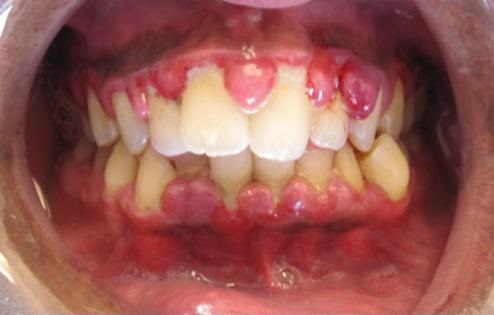

피나고 붓는 잇몸, 인사돌로 나을 수 있나?

1. 국민 잇몸약 인사돌 "이가 흔들리고 잇몸에서 피가 나는데 인사돌을 처방해 줄 수 있는가?" 라고 묻는 사람들이 간혹 있습니다. 인사돌을 잇몸 치료제로 생각하고 물어보는 것입니다. 워낙 광고로 친숙한 약이다 보니 그 효과에 대해 환상과 오해가 있는 편입니다. 오늘은 가정의학과 의사의 시선에서 인사돌의 핵심 성분인 '옥수수불검화물(ETAS)'의 정체와 그 의학적 한계, 그리고 올바른 활용법에 대해 깊이 있게 다뤄보겠습니다. 2. 인사돌의 핵심 성분: 옥수수불검화물(ETAS)이란? 인사돌은 옥수수의 눈(배아)에서 추출한 기름 중 비누화되지 않는 미세 성분(불검화물)을 정제한 것입니다. ** 불검화물이란: 식물이 종자를 보호하기 위해 기름 속에 섞어둔 '천연 약성 성분'으로, 기름 속에 섞인 일종의 ..